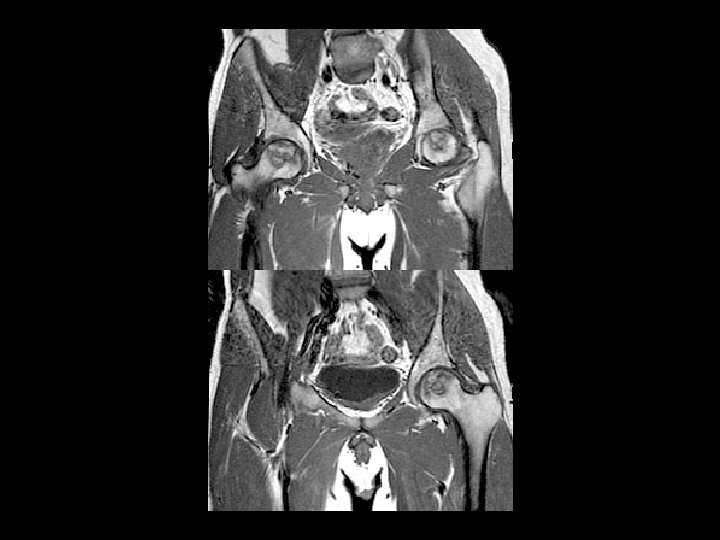

Femoral Head AVN • Findings: – bilateral femoral head AVN w/o collapse – right pelvic renal tx